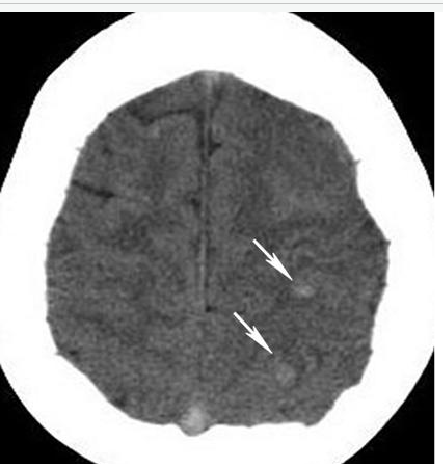

The scenano depicted above is indicative of intracerebral hemorrhage from cerebral sinus thrombosis, making anticoagulation with continuous intravenous heparin infusion the most appropriate answer. Small hernorrhages are evident on CT (white arrows). as well as a hyperdense superior sagittal sinus. Likely representing sinus thrombosis. The diagnosis of sinus thrombosis is reinforced by the clinical history of recent childbirth; cerebral sinus trombones is more likely in patients with a hypercoagulate state, such as the peripartum period (within 16 days of childbirth). Intracerebral hemorrhage often secondarily occurs in patients with cerebral sinus thrombosis due to venous hypertension. Treatment goals for a patient with sinus thrombosis are prevention of further thrombosis and recanalization of the occluded sinus. Initial treatment should be administration of anticoagulation with a continuous intravenous heparin infusion.